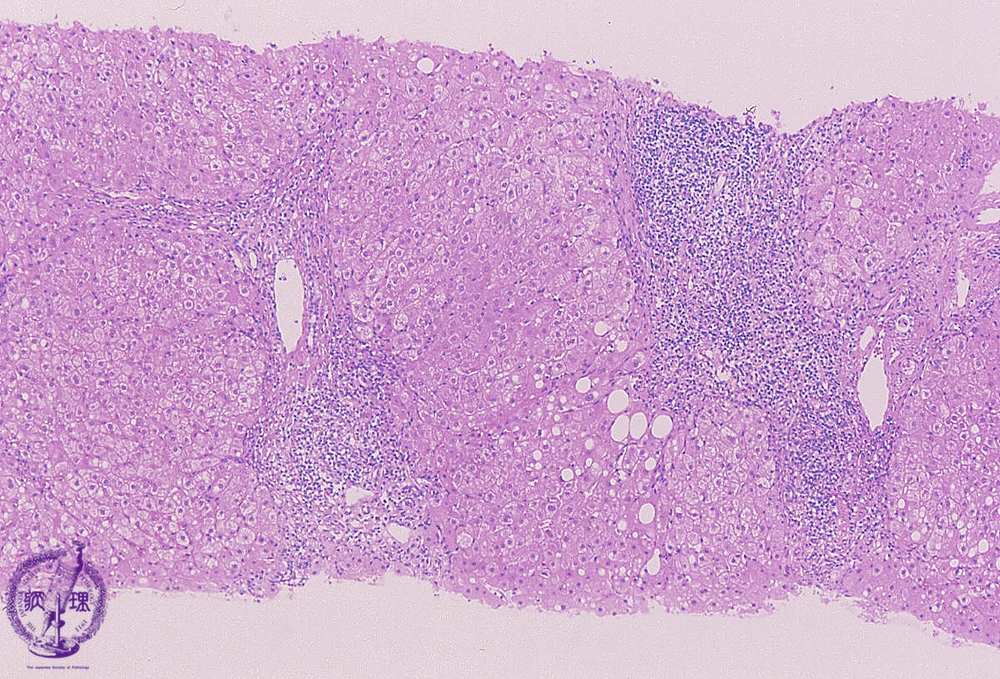

Microscopic image (HE stain, low power view): There is a dense lymphocytic infiltrate with corresponding moderate to marked portal expansion (yellow circle). Fibrosis (blue line) is also seen, and results in disruption of the lobular architecture with segregation of lobules which imparts a nodular appearance in some areas (blue area).